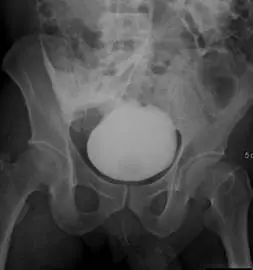

一名成年男性病人車禍後主訴下腹部疼痛和血尿,逆行性膀胱攝影檢查呈現如附圖。下列有關膀胱的初診斷何者最恰當?

膀胱破裂依據尿液或造影劑漏出位置,可分為 intraperitoneal rupture(腹內破裂)與 extraperitoneal rupture(腹外破裂)。影像學上,intraperitoneal rupture 會使對比劑散佈於腹腔,並沿腸袢及腸繫膜間隙流動;extraperitoneal rupture 則限於膀胱周圍的前縱隔或 Retzius 隙,呈現「火焰狀」或「門牙狀」的局限性外漏。Retrograde cystogram(逆行性膀胱攝影)為此類傷害的影像學黃金標準,必須以足量(約 300–350 mL)對比劑充分填充膀胱,並拍攝注射後與排空後影像以免漏診。(pmc.ncbi.nlm.nih.gov)

影像分析:

影像為逆行性膀胱攝影前導平片(AP view),可見膀胱腫脹、充滿高密度對比劑。對比劑並非僅侷限於膀胱輪廓內,而是溢散至骨盆以上,形成不規則分佈的濃度,並沿骨盆外緣及腸袢周圍分佈,呈現環繞腸袢的對比劑影—典型的 intraperitoneal contrast extravasation 表徵。未見集中於骨盆周圍之纖維囊狀或火焰狀外漏,亦不符合 pseudodiverticulum(偽